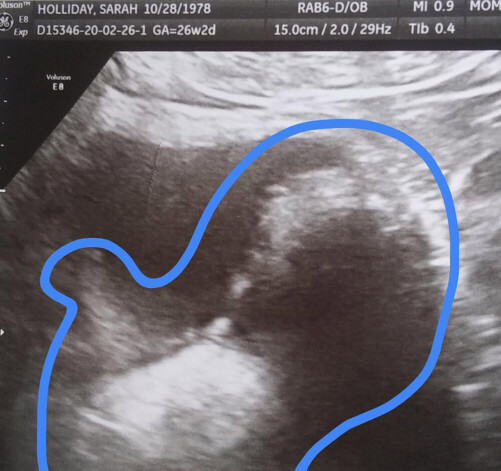

Sieviete ir pārliecināta, ka jau trīsarpus gadus iznēsā bērnu, un apstiprina to ar ultrasonogrāfiju

Sāra dzīvo ASV ziemeļu pilsētā Fortkolinsā. 2016. gada jūlijā sieviete uzzināja, ka kļūs par māti, bet tā paša gada oktobrī mediķi sāka uztraukties. Līdz tam laikam auglim jau vajadzēja saklausīt sirdsdarbību, taču tas tā arī nenotika. Dīvaini, bet vēders turpināja augt. Holideja uzskata, ka cieš no „kripto grūtniecības” – grūtniecība, ko mūsdienu testēšanas metodes vienkārši nespēja konstatēt.